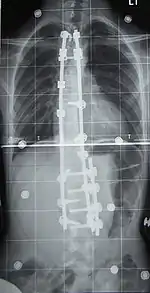

Fusión vertebral con instrumentación

La fusión espinal es la cirugía que más se realiza para la escoliosis. En este procedimiento, el hueso (ya sea cosechado en otras partes del autoinjerto cuerpo o de un injerto de donantes) es injertado en las vértebras de manera que cuando se cura se va a formar una masa ósea sólida y en la columna vertebral se vuelve rígido. Esto previene el empeoramiento de la curva a expensas de algunos movimientos de la columna. Esto puede ser realizado desde la anterior (frontal) los aspectos de la columna vertebral por entrar en la cavidad torácica o abdominal, o más comúnmente realizado desde la parte trasera (posterior). Una combinación se utiliza en los casos más graves.

Originalmente, las fusiones espinales se hicieron sin los implantes de metal. Un reparto se aplicó después de la cirugía, generalmente bajo la tracción para tirar de la curva lo más recto posible y mantenerla allí mientras que la fusión se llevó a cabo. Desafortunadamente, había un riesgo relativamente alto de la pseudoartrosis (no fusión) en uno o más niveles y corrección significativa no siempre podían ser alcanzados.

En 1962, Paul Harrington, introduce un sistema de instrumentación de la columna vertebral de metal, que ayudó a enderezar la columna vertebral, así como la celebración es rígido, mientras que la fusión se llevó a cabo. El original, barra de Harrington obsoleto opera en un sistema de trinquete, atribuida por los ganchos de la columna en la parte superior e inferior de la curvatura que, cuando se privaría de manivela, o enderezar la curva. Una deficiencia importante del método de Harrington fue que no pudo producir una postura en el cráneo, estaría en la correcta alineación con la pelvis y no se ocupa de la deformidad de rotación. Como resultado, las partes no usado de la columna se tratan de compensar esto en el esfuerzo de mantenerse derecho. Como la persona mayor, no se aumenta el desgaste, la artritis de inicio temprano, la degeneración del disco, la rigidez muscular y el dolor con la dependencia final sobre los analgésicos, cirugía adicional, la incapacidad para trabajar a tiempo completo y la discapacidad. "FlatBack" se convirtió en el nombre médico para una complicación relacionada, sobre todo para aquellos que tenían escoliosis lumbar.

Los sistemas modernos espinal están tratando de resolver el desequilibrio sagital y sin resolver los defectos de rotación por el sistema de barras de Harrington. Que implican una combinación de varillas, tornillos, ganchos y alambres de fijación de la columna vertebral y puede solicitar más fuerte, más seguro para las fuerzas de la columna vertebral de la barra de Harrington. Esta técnica se conoce como la Cotrel instrumentación Dubousset, actualmente la técnica más común para el procedimiento.